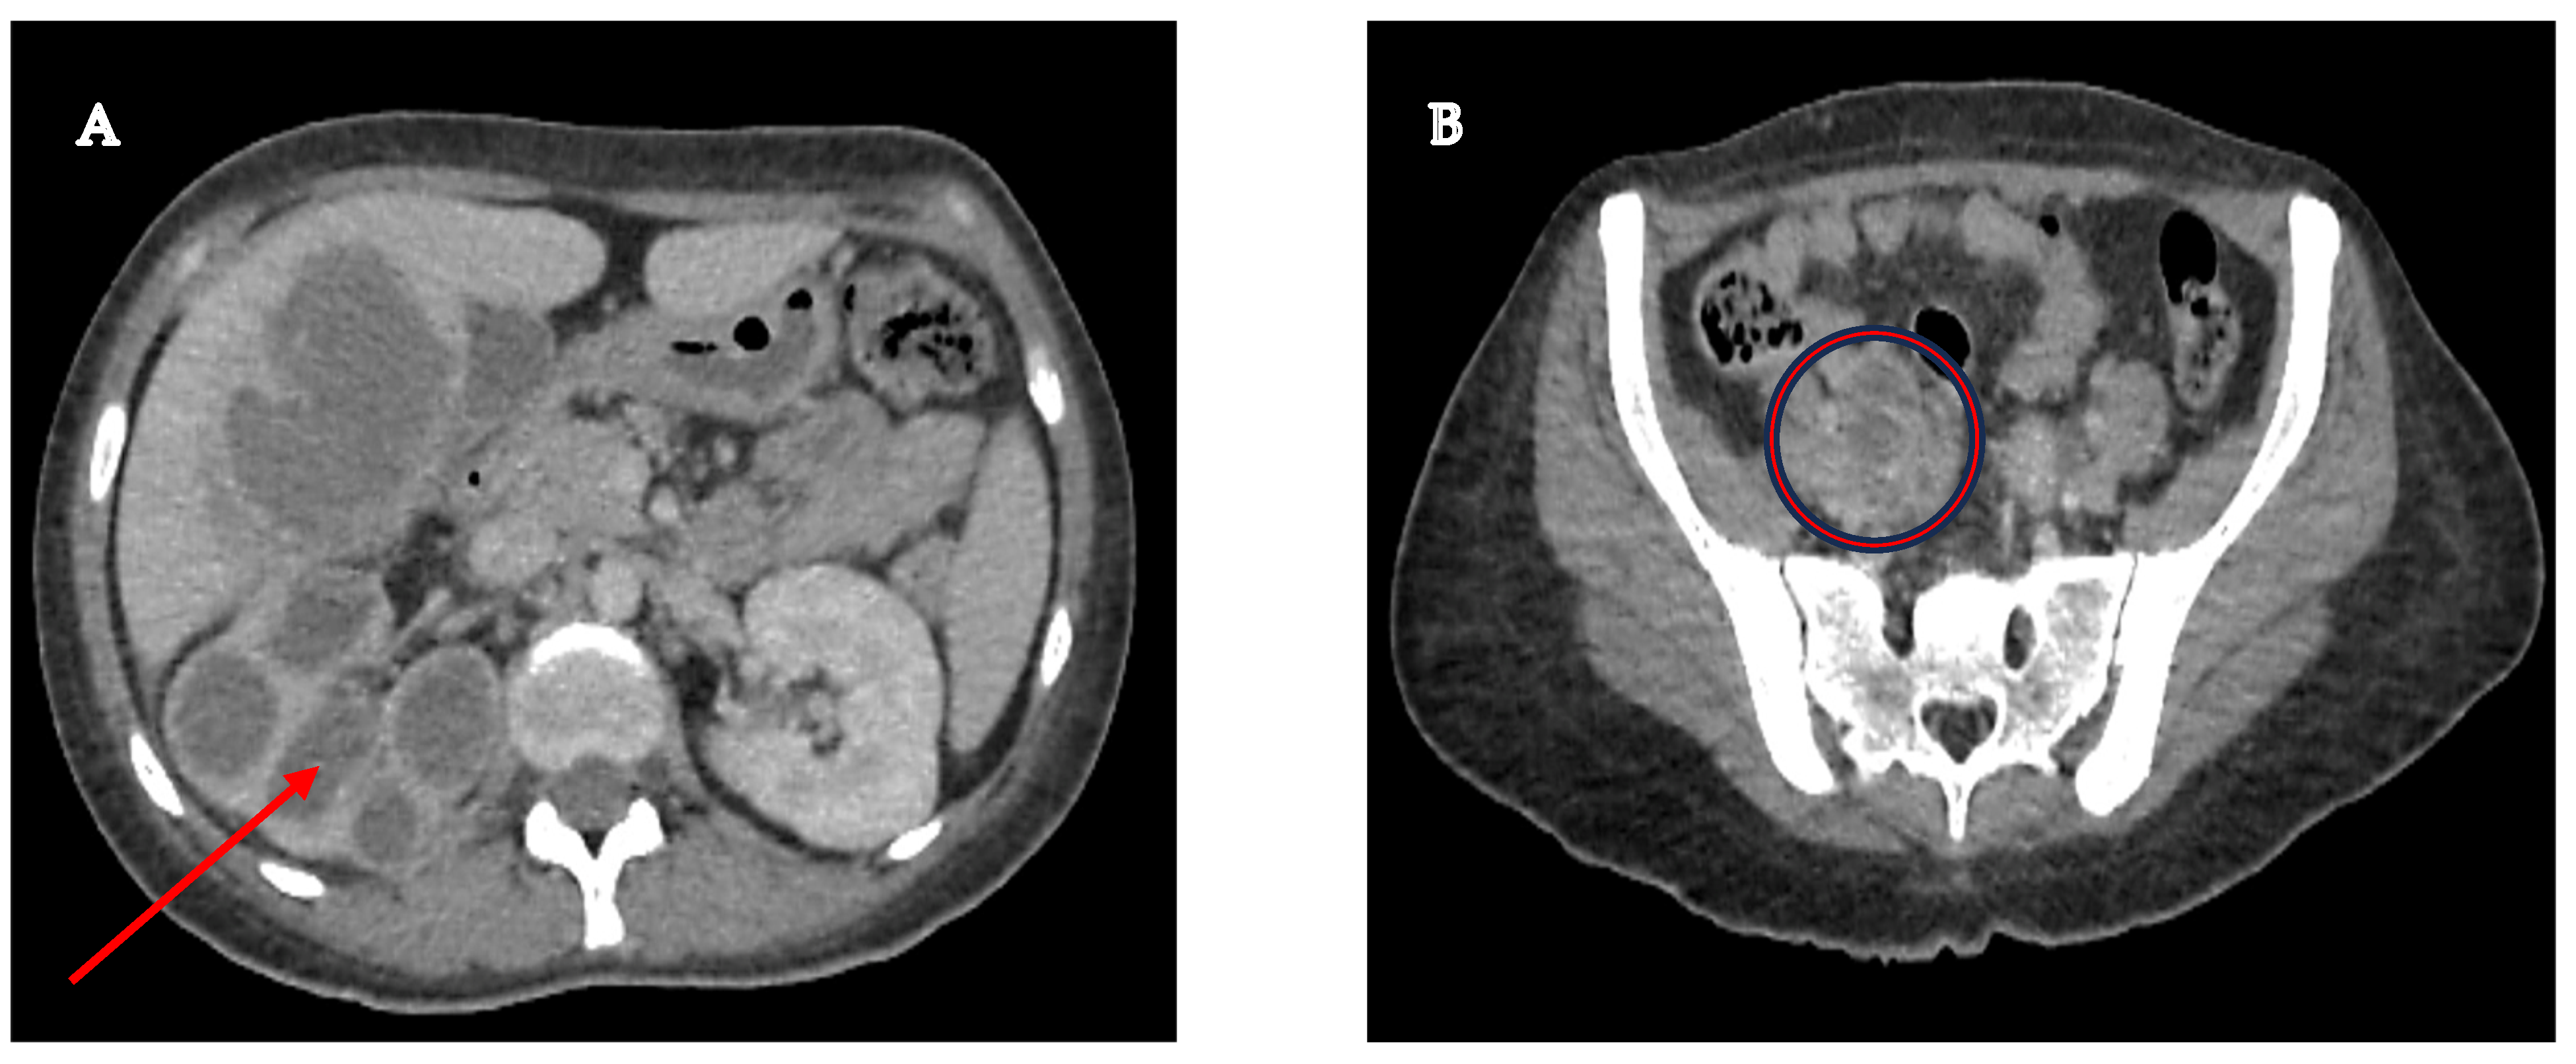

A 33-year-old female patient had a history of type 2 Diabetes Mellitus under suboptimal control and without other risk factors for immunocompromise, with a history of recurrent urinary tract infections and use of multiple outpatient antibiotic regimens in the last year before admission. The patient arrived at the emergency room with a condition characterized by pain in the right renal fossa that radiated to the right hypochondrium, fever with chills, nausea, and vomiting. Upon arrival at our hospital, the vital signs showed blood pressure of 113/64 mmHg, temperature of 38.3 °C, heart rate of 99 bpm, respiratory rate of 21 rpm, and oxygen saturation of 97% in room air. Physical examination revealed a positive Giordano’s sign and positive ipsilateral middle and upper ureteral points. Therefore, laboratory studies were requested, where it was identified as iron deficiency anemia with hemoglobin of 10.3 g/dL, leukocytes of 10,500 cells/mcl with neutrophilia of 78%, platelets of 614,000/mcl, metabolic decontrol with fasting glucose of 240 mg/dL, preserved renal function with creatinine of 0.78 mg/dL, and elevated alkaline phosphatase of 156 IU/L and gamma-glutamyl transpeptidase of 51 IU/L. Additionally, the general urine examination showed negative nitrites, erythrocytes 10–25 by field, leukocytes 5–10 by field, epithelial cells 2–5 by field, and abundant mucoid filaments, suggesting urinary tract infection. Therefore, antibiotic coverage with ceftriaxone was started after collecting blood and urine samples. Additionally, as part of the care protocol, at least two peripheral blood culture vials (10 mL) were processed. Blood cultures were performed in BD Bactec™ Plus Aerobic/F and BD Bactec™ Anaerobic/F culture vials and incubated at 35 ± 2 °C in the BD BACTECT™ Blood Culture System (Becton Dickinson, Franklin Lakes, NJ, USA). However, the etiologic agent was not successfully isolated from the blood cultures. A urine sample was cultured in 5% sheep blood agar and MacConkey agar, yielding the same results as the blood cultures. A contrast-enhanced tomographic study highlighted a tumor that infiltrated the distal third of the right ureter with retrograde dilatation, an ipsilateral kidney with hydronephrosis and pyeloureteral dilatation, and a liver lesion with a liquid and solid component (Figure 1).

Figure 1.

(A) Right kidney with significant cortical thinning, accompanied by ureterohydronephrosis (red arrow), suggesting a possible chronic obstruction of the urinary tract; (B) Pelvic mass measuring 46 × 25 mm, seemingly originating in the lumen of the right ureter, with infiltration into its distal third (red circle), a finding that raises a differential diagnosis between a urothelial tumor and a severe inflammatory infectious process.